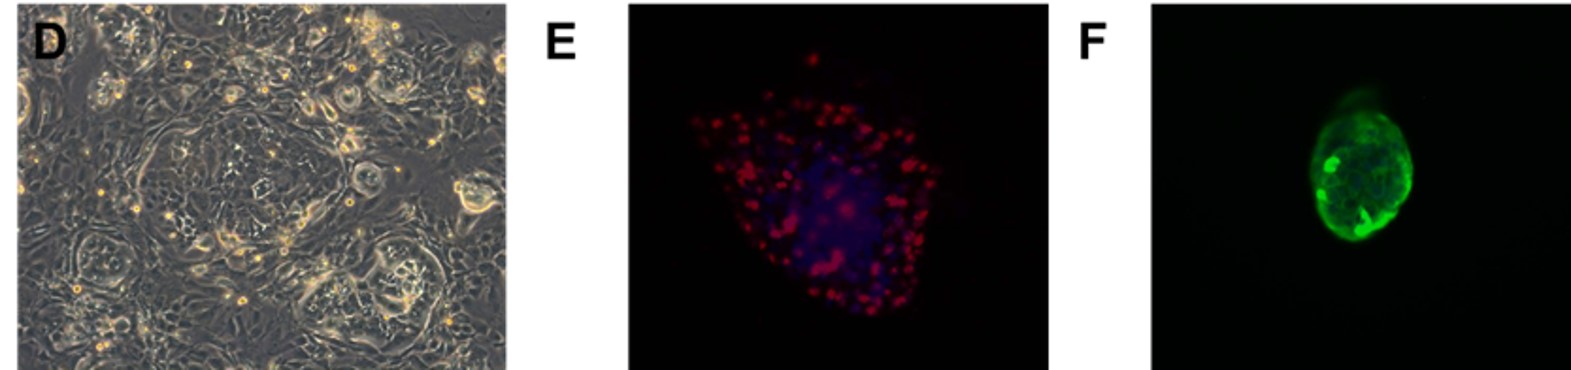

Fig. Morphology of EGFR 19del/T790M /C797S PDX derived cell line (D); Ki67 (E) and Pan-CK (F) staining of 19del/T790M /C797S PDX matching cell derived tumor sphere.